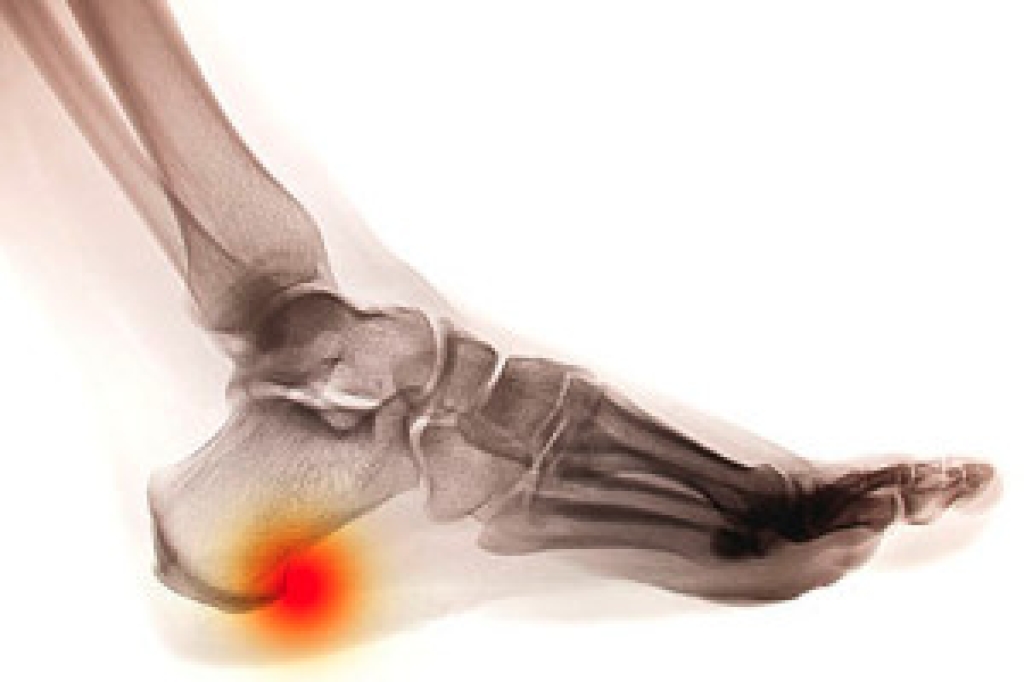

Heel spurs